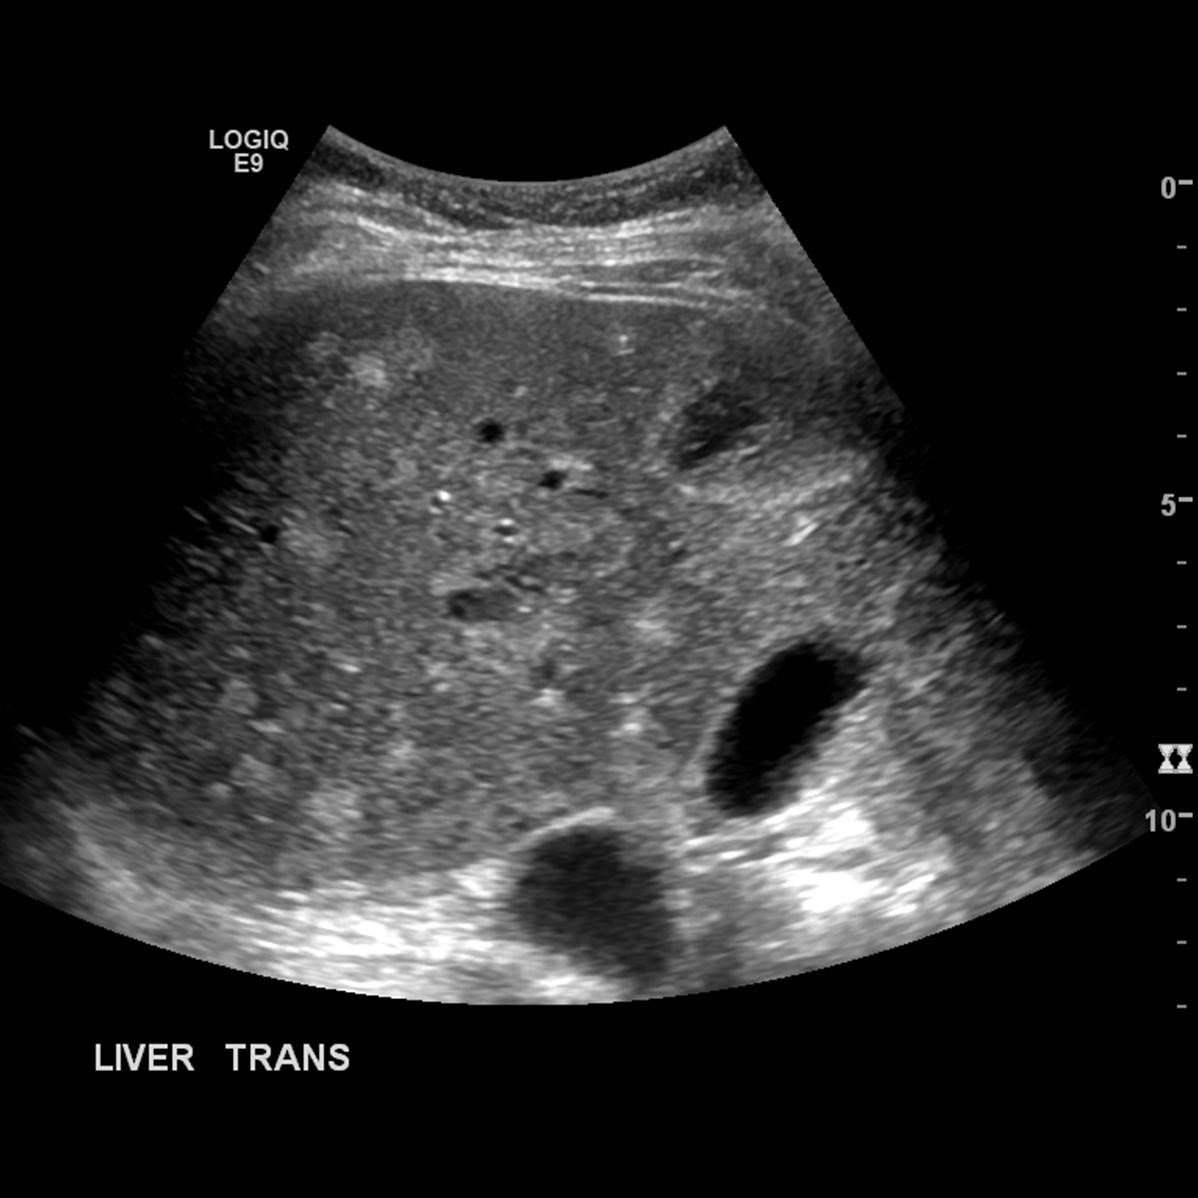

PVT diaqnozunu dəqiqləşdirmək üçün portoqrafiya aparılır – Doppler USM, KT və ya MRT angioqrafiya.

Portoqrafiya – Doppler USM, KT və ya MRT angioqrafiya;

- portoqrafiyada vena mənfəzində trombun görünməsi;

- venanın distalında genişlənmə və kavernoz transformasiyanın görünməsi;